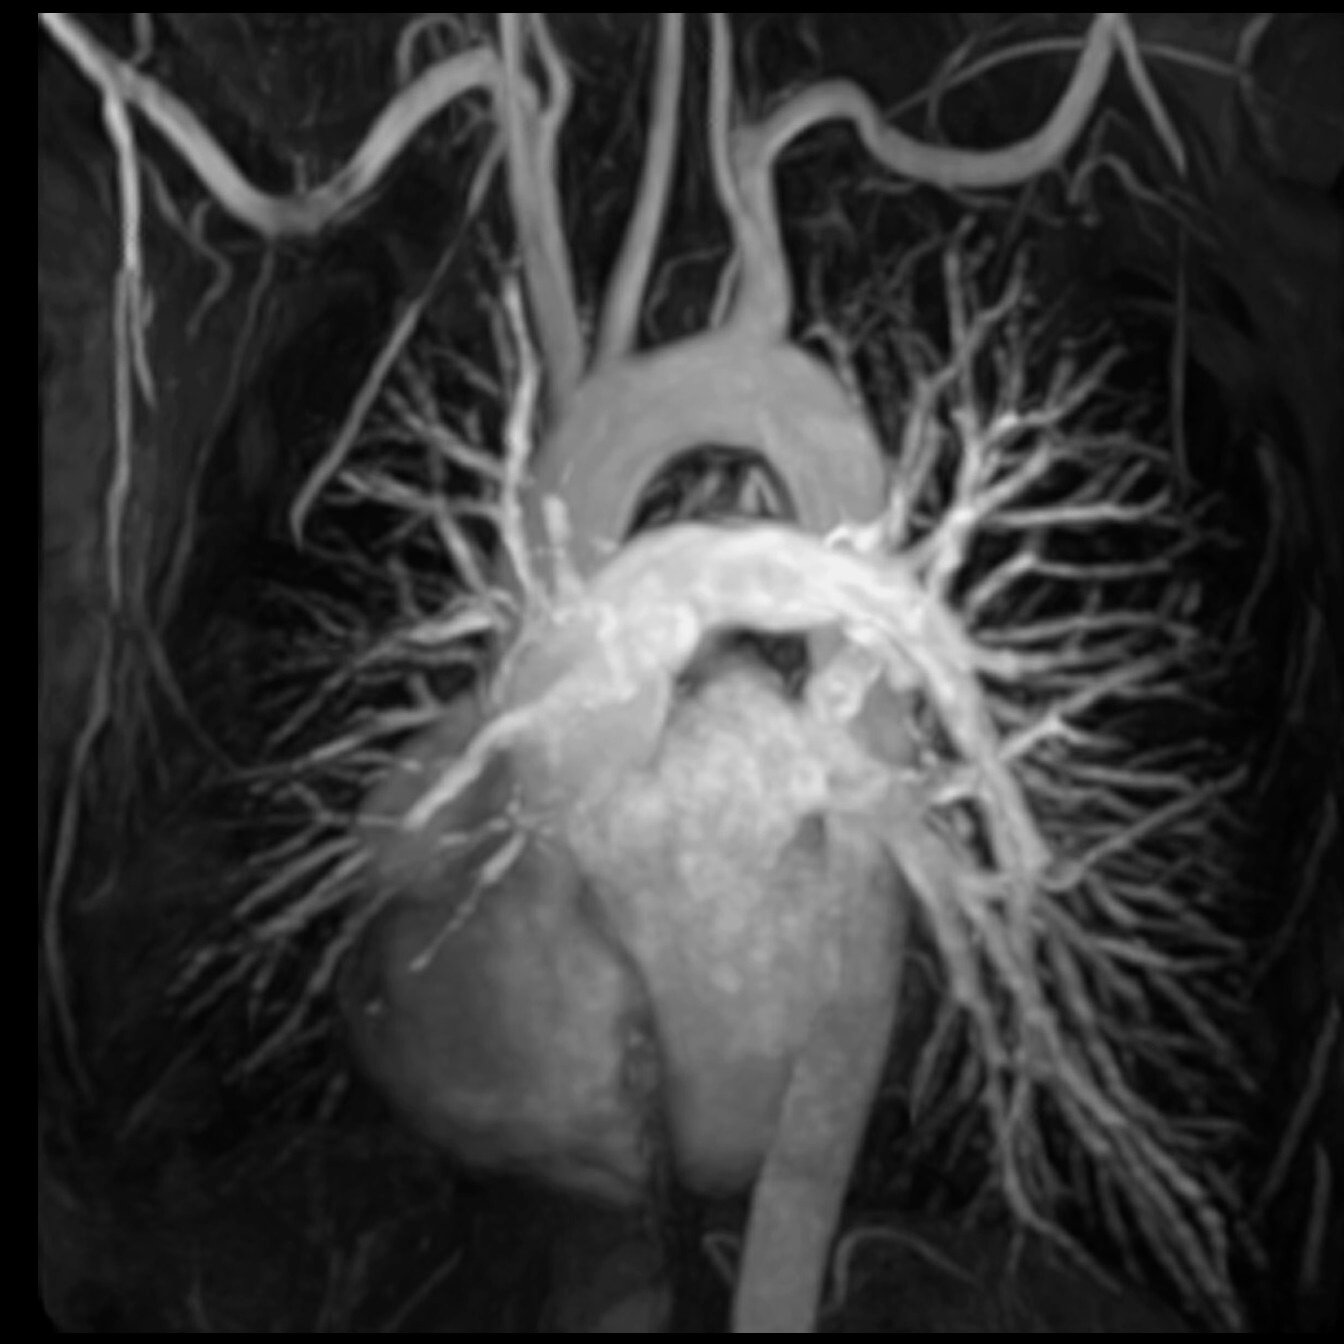

Cardiac

Vascular